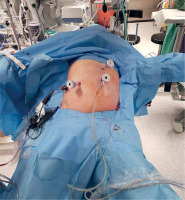

PM should be prepared before parenchymal transection for possible immediate application. It can be performed intracorporeally and extracorporeally. For an intracorporeal PM a long cotton tape is placed around the hepatoduodenal ligament through a 12 mm trocar, then passed through a small tourniquet and clipped 2–3 cm above it. For occluding the hepatic inflow, the tourniquet is pushed toward the hepatic pedicle and clipped above it. Pedicle clamping may also be performed with a laparoscopic bulldog clamp or appropriately prepared Foley’s catheter (Photo 3) [22]. For an extracorporeal PM the tape is externalized through a trocar and passed through the catheter placed above the trocar. The main advantage of the extracorporeal technique is the possibility for clamping by the assistant surgeon, without distraction of the main surgeon (Photo 4). When comparing both techniques of PM in retrospective studies, extracorporeal PM carries more practical advantages, but it still requires further research [23]. PM can be continuous or intermittent (most commonly 15 : 5 min ratio or 10 : 5 min ratio in cirrhotic liver). In HCC patients, according to a recent RCT, 25 min intermittent PM results in lower BL, as well as higher transection speed [24]. However, the performed PM technique depends on surgeons’ preferences and estimated operative time.

There are various techniques to reduce hepatic venous congestion and therefore intraoperative BL, the main one being restrictive fluid therapy. Both absolute fluid restriction and relative volume redistribution are comparable techniques, as long as low CVP or high SVV is achieved [59]. Goal-directed fluid therapy, suited individually to the patient, is a recommended approach [64]. To pharmacologically control low CVP during LLS anesthesia, milrinone may be a better choice than nitroglycerin, reducing intraoperative BL, but there are no data related to LLS [65]. Other research confirms decreased BL and TR when using terlipressin infusion to maintain low CVP [66]. The reverse Trendelenburg position, used commonly in LLS, also helps to reduce intraoperative BL (Photos 9 and 10) [67]. Pneumoperitoneum, with its overall positive effects on reducing intraoperative BL, should be between 10 and 14 mm Hg [68], but it could be temporarily increased in dire situations to help control bleeding during LLS [69].